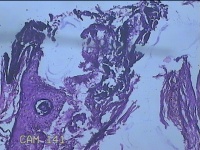

左眼外侧缘上肿物

性别

女

年龄

60岁

临床诊断

痣;疣

左眼上睑缘白色丘疹1年余。

灰白粉红色肿物0.8x0.3x0.2cm两个,表面光滑。

图3